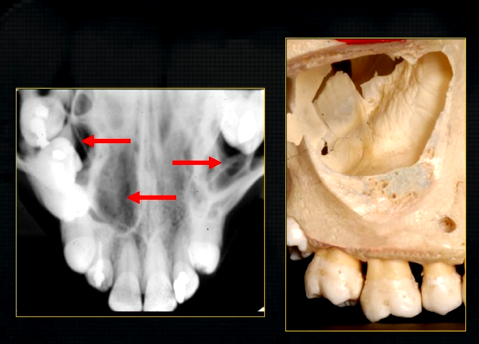

resultant radiographs are always 2d demonstrations of a 3d object - all structures, internal and external will be superimposed on one another

how the anatomy is presented geometrically is dependent on the relative positions of the patient, image receptor and the X ray beam

what does this anterior periapical graph show?

oval radiolucent area between the central incisors - is it Infront of the teeth (buccally?) or is it behind them? - you can’t tell radiographically

but its shape and position is compatible with the palatally positioned with the nasopalatine formaina

more posteriorly - radiopacities indicate the nasal septum and floor of the nose

dense, thin , white line in the middle of the image is the nasal septum

less dense opacity is caused by the

inferior nasal concha

radiolucency - nasal septum

lateral wall of the nose

maxillary air sinus

mid-palatal suture

this increased radiopacity is caused by the soft tissues at the tip of the nose - shadow - dense tissue